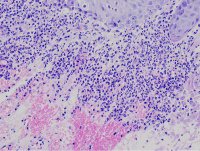

外阴多发赘生物,请教老师们,怎么报告?

性别

女

年龄

62

发现外阴数十粒丘疹样结节,伴溃疡

外阴丘疹样赘生物

灰白色组织两粒0.5*0.3cm

考虑:疱疹病毒感染

疱疹性皮炎。

符合疱疹性皮炎。